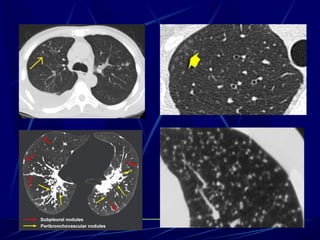

Notice the nodules along the fissures indicating a

perilymphatic distribution (red arrows).

The majority of nodules located along the bronchovascular

bundle (yellow arrow).